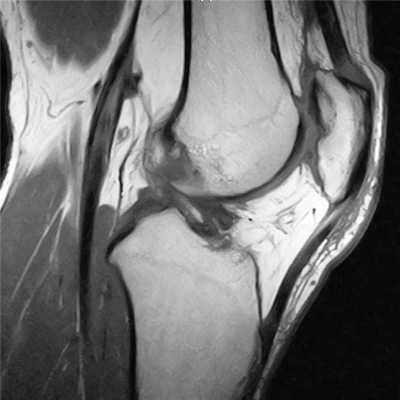

повреждение хряща и субхондрального слоя внутреннего мыщелка бедреной кости

2. ЯМРТ (ядерно-магнитно-резонансная томография) Современный, высокоинформативный, безопасный метод исследования. Лучше всего подходит для определения мягкотканых повреждений: связочного аппарата, повреждений менисков, хряща и др.

разрыв крестообразных связок коленного сустава (изображение слева), разрыв заднего рога внутреннего мениска коленного сустава (изображение справа)